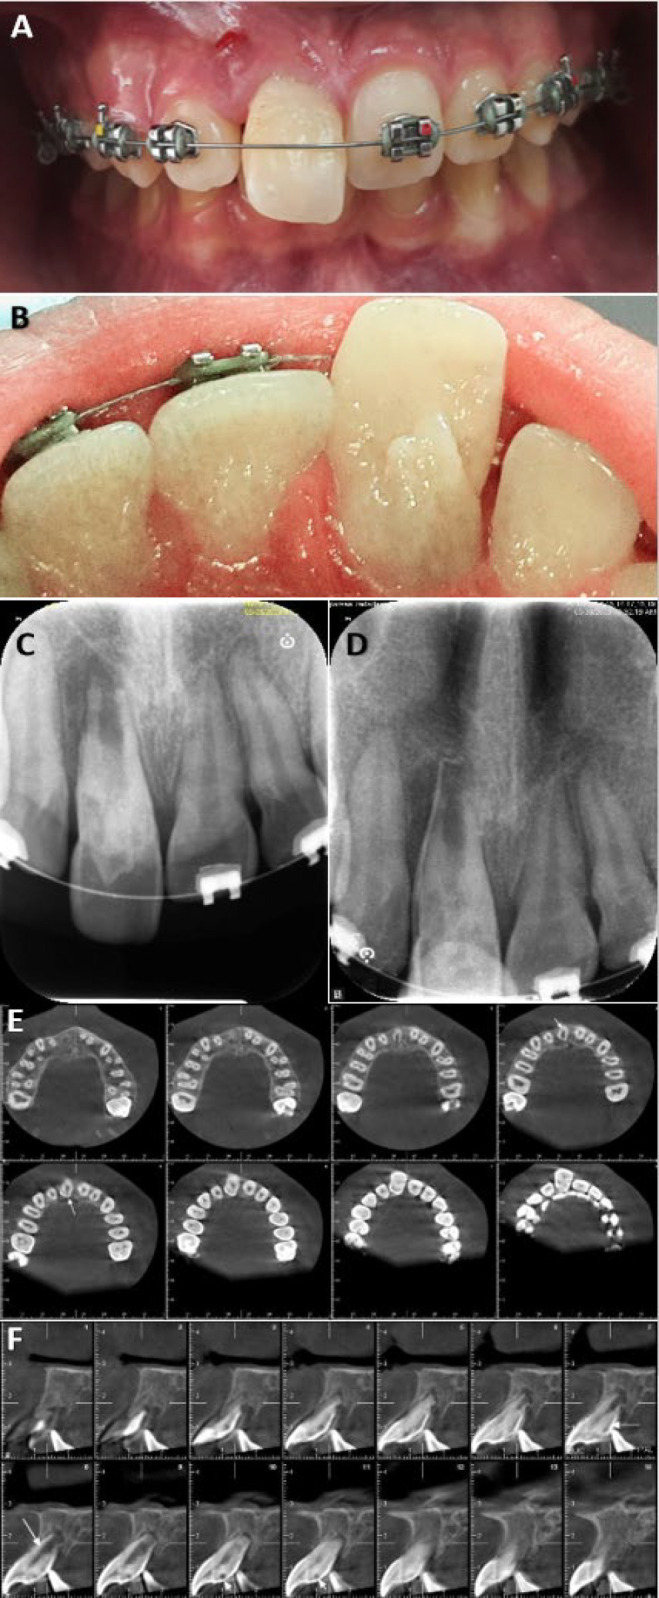

内凹牙是由于牙釉质和牙本质向牙髓内折叠而引起的发育异常。Oehlers的IIIa型牙槽内陷由于其复杂的解剖结构和经常与未成熟牙齿相关而面临重大挑战。本病例报告概述了一个非重要的未成熟上颌中切牙IIIa型牙槽内陷的非手术治疗,表现为慢性根尖脓肿和相关的上切牙创伤史。治疗包括彻底的化学机械清创,然后使用富钙混合水泥进行生物封闭。定期随访发现根尖周围病变完全消退。这个病例强调了精确诊断、个体化治疗计划和应用先进生物材料在解决复杂凹牙表现的重要性。成功的结果强调了非手术技术在保留未成熟牙齿的同时恢复功能和美观的有效性。

Dens invaginatus is a developmental anomaly resulting from the infolding of enamel and dentin into the dental pulp. Oehlers' Type IIIa dens invaginatus poses significant challenges due to its intricate anatomy and frequent association with immature teeth. This case report outlines the nonsurgical management of a nonvital immature maxillary central incisor with Type IIIa dens invaginatus, presenting with a chronic apical abscess and a history of trauma to the associated primary incisor. Treatment involved thorough chemomechanical debridement followed by bio-obturation using calcium-enriched mixture cement. Regular follow-ups revealed complete resolution of the periapical lesion. This case underscores the importance of precise diagnosis, individualized treatment planning, and the application of advanced biomaterials in addressing complex presentations of dens invaginatus. The successful outcome emphasizes the efficacy of nonsurgical techniques in preserving immature teeth while restoring function and aesthetics.